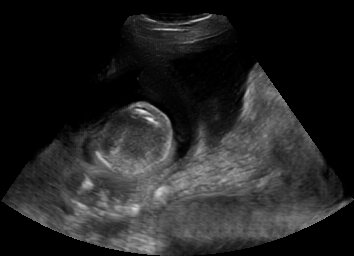

Real in-vivo images. 22 ultrasound sequences were collected using a GE Voluson E8 machine during standard fetal screening exams of 8 patients. Each sequence is several seconds long. We extracted all 4427 frames and resize them to , see Fig. 2 for some examples. The resulting image set was randomly split into training-validation-test sets by a 80-10-10% ratio.